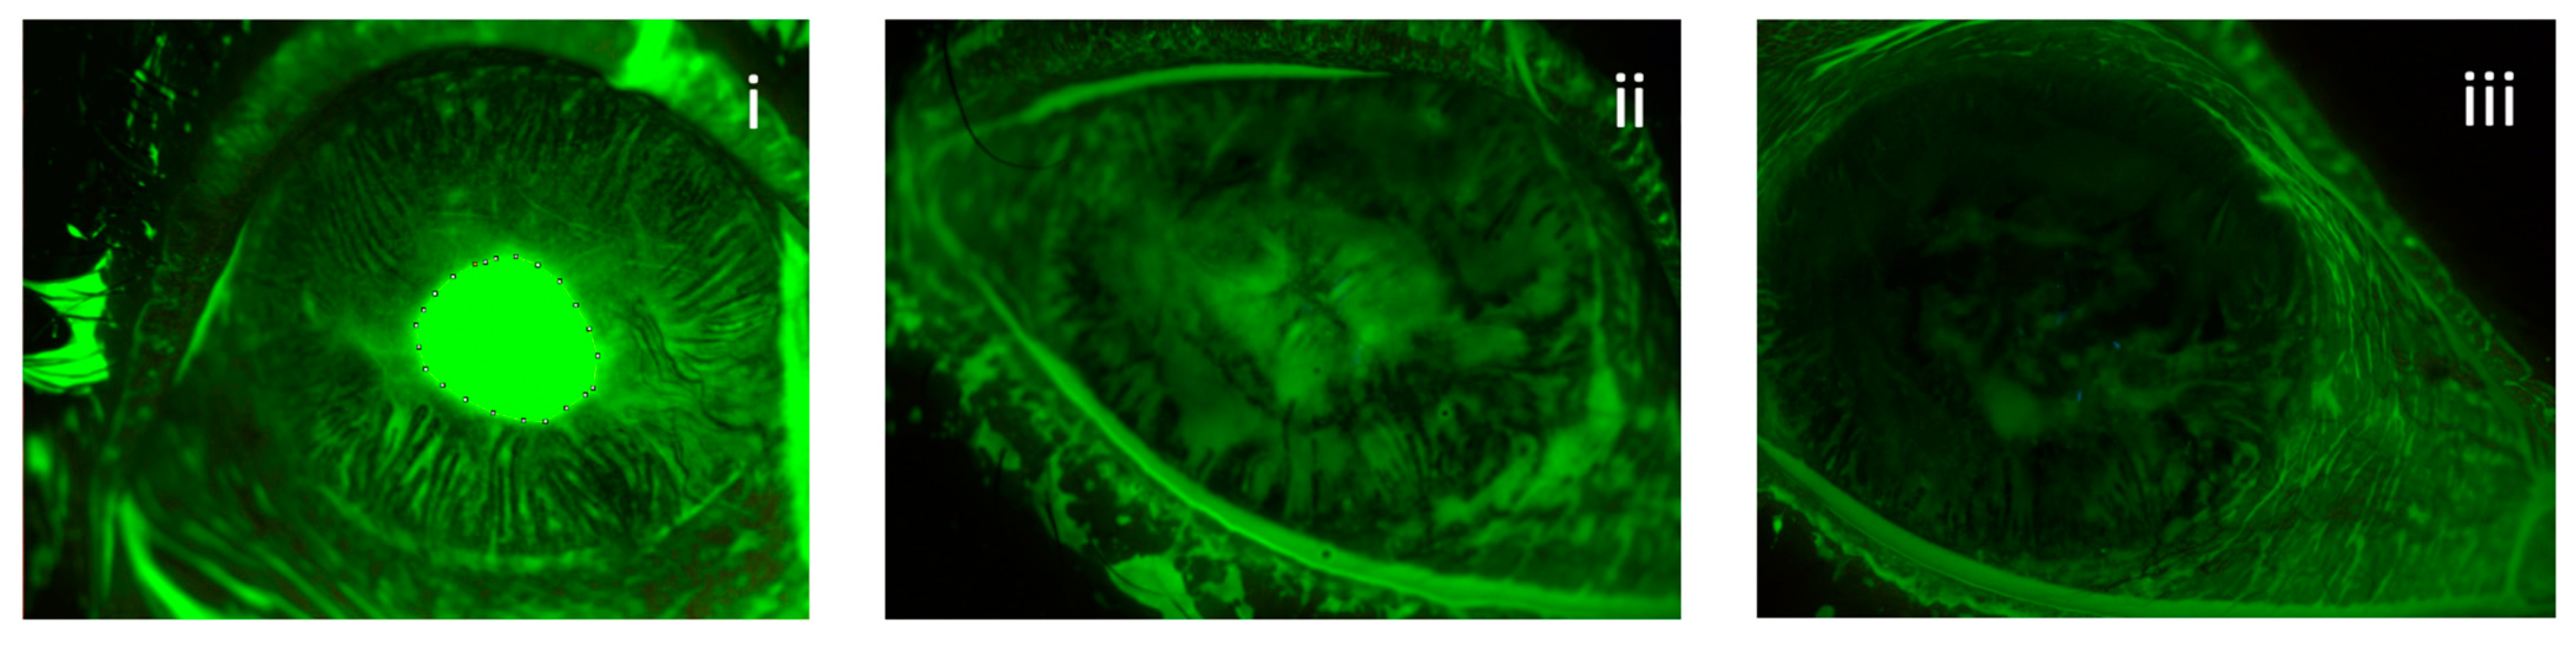

3.1. Area of Ulcers

3.3. Corneal Nerves